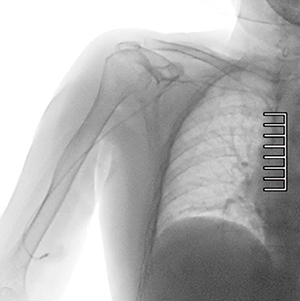

症例1 CVポート抜去術における抜去直前の全体透視像

CV専用の画像処理を構築することで,通常では描出困難であった高吸収域から低吸収域にまたがる1本のカテーテルが,非常に明瞭に観察可能となった。